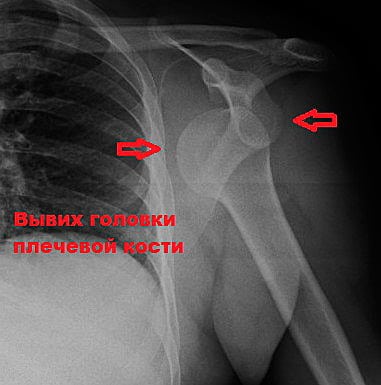

Разрыв связок плечевого сустава всегда сопровождает вывихи плеча и ключицы. В этом случае нарушение целостности связочного аппарата возникает из-за смещения костей. Они тянут прикрепленные к ним связки, из-за чего те с легкостью рвутся. При вывихах плеча часто страдают еще и мышечные сухожилия.

В некоторых источниках вы можете встретить аббревиатуру АКС — это акромиально-ключичное соединение. Именно разрыв АКС плечевого сустава обычно приводит к вывиху ключицы. При повреждении других связок целостность соединения может сохраняться.

Исключить переломы и вывихи, отличить разрыв от болезней с похожей клинической картиной можно лишь с помощью дополнительных методов исследования.

| Рентгенография | Позволяет увидеть только костные структуры. Мягкие ткани на рентгенограммах не визуализируются. Исследование назначают всем пациентам с травмами плеча | С помощью рентгенографии можно исключить вывихи ПС и АКС, переломы костей верхней конечности и плечевого пояса |